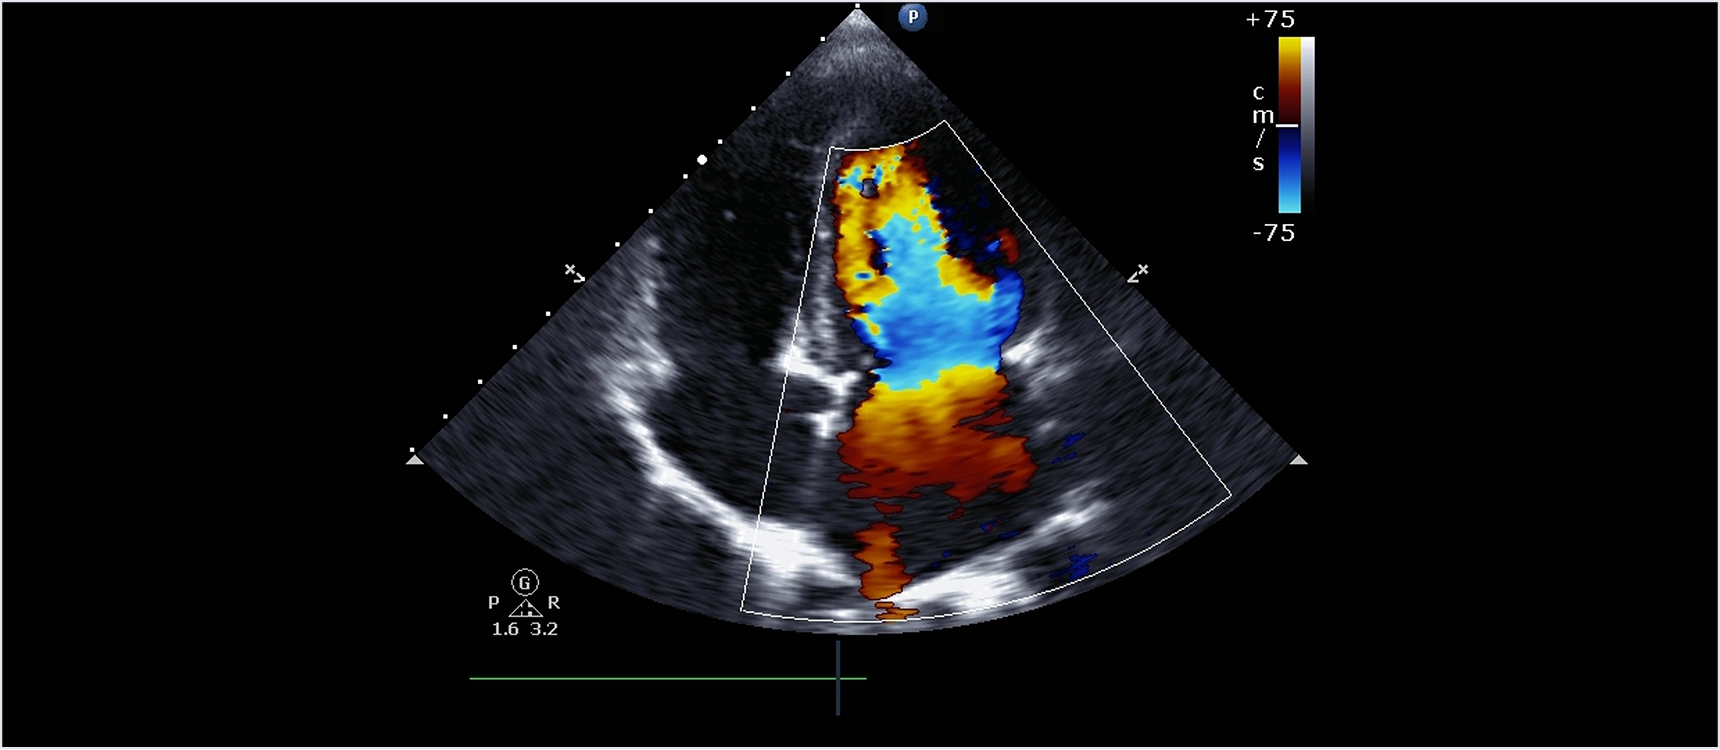

심장 초음파란?

심장에 초음파를 발사하여 심장의 구조, 크기, 기능을 실시간으로 평가하는 검사입니다. 통증이나 위험 없이 심장 내부를 직접 관찰할 수 있어, 판막질환, 심근병증, 협심증, 심근경색 등 다양한 심장질환을 진단할 수 있습니다.

진단 범위